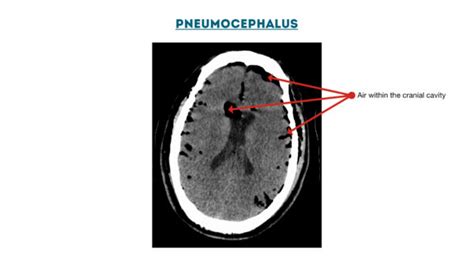

Diagnosis: How Doctors Find the Air

So, you’re experiencing some weird symptoms, and your doctor suspects pneumocephalus . How do they actually figure out if there’s air in your head? Well, it’s usually a combination of a thorough medical history, a physical examination, and most importantly, medical imaging. The doctor will ask about any recent head injuries, surgeries, or medical procedures you’ve undergone. They’ll also perform a neurological exam to check your reflexes, coordination, strength, and mental status. The real stars of the show, though, are the imaging techniques. Computed Tomography (CT) scan of the head is the gold standard for diagnosing pneumocephalus. CT scans are excellent at visualizing bone and detecting air, which appears as very dark areas on the scan. Doctors can clearly see the location and amount of air within the cranial cavity. They often look for a characteristic